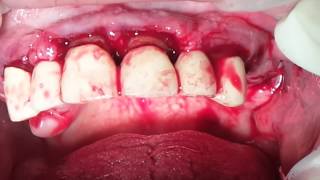

Видеоролик с операцией с практического семинара "Пластика мягких тканей и пародонтальная хирургия" 23-25 декабря 2013 года. М.А. Носова, стоматолог-хирург-пародонтолог. ТМО используется вместо СТТ с неба. Результат отличный. За 4 месяца ТМО полностью замещается соединительной тканью.

Видео демонстрирует пошаговую методику использования твердой мозговой оболочки (dura mater) для увеличения объема прикрепленной десны в области рецессии. Запатентованная методика в России. Дает 100%-ный результат при хирургическом лечении рецесии.

Мария Александровна Носова, врач-стоматолог-хирург-пародонтолог подробно рассказывает методику установки ТМО dura mater в область рецессии десны. ТМО устанавливается в "расщепленный"  лоскут и при необходимости фиксируется швами к зубам, к лоскуту или к надкостнице.

Лечение множественных рецессий М.А. Носова проводит с использованием ТМО (dura mater) c 2010 года. Использование ТМО вместо свободного тканевого трансплантата позволяет исключить вторую операцию по забору СТТ. Результат 100%-ный во всех случаях.